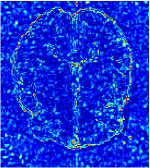

All the experiments are implemented on a Windows workstation with Intel Core i9 CPU at 3.3GHz and an Nvidia GTX-1080Ti GPU with 11GB of graphics card memory via TensorFlow Abadi et al. (2016). The parameters in the proposed network are initialized by using Xavier initialization Glorot and Bengio (2010). We trained the meta-learning network with four tasks synergistically associated with four different CS ratios: 10%, 20%, 30%, and 40%, and test the well-trained model on the testing dataset with the same masks of these four ratios. We have 300 training data for each CS ratio, which amount to total of 1200 images in the training dataset. The results for and MR reconstructions are shown in Tables 5.4 and 5.4 respectively. The associated reconstructed images are displayed in Figures 1 and 3. We also test the well-trained meta-learning model on unseen tasks with radio masks for skewed ratios: 15%, 25%, 35%, and random Cartesian masks with ratios 10%, 20%, 30% and 40%. The task-specific parameter for the unseen tasks are retrained for different masks with different sampling ratios individually with fixed task-invariant parameters . In this experiments, we only need to learn for three skewed CS ratios with radio mask and four regular CS ratios with Cartesian masks. The experimental training proceed on less data and iterations, where we performed on 100 MR images with 50 epochs. For example, for reconstructing MR images with CS ratio 15% radio mask, we fix the parameter and retrain the task-specific parameter on 100 raw data with 50 epochs, then test with renewed on our testing data set with raw measurement that sampled from radio mask with CS ratio 15%. The results associated with radio masks are shown in Table 5.4 and 5.4, Figure 2 and 4 for and images respectively. The results associated with Cartesian masks are list in Table 5.4 and reconstructed images are displayed in Figure 5.

Qualitative comparison between conventional and Meta-learning methods are shown in Figure 1 and 3, which display the reconstructed MR images of the same slice for T1 and T2 respectively, we label the zoomed-in details of HGG in the red boxes. We observe the evidence that conventional learning is more blurry and lost sharp edges, especially in lower CS ratios. From the point-wise error map, we find meta-learning has the ability to reduce noises especially in some detailed and complicated regions comparing to conventional learning.